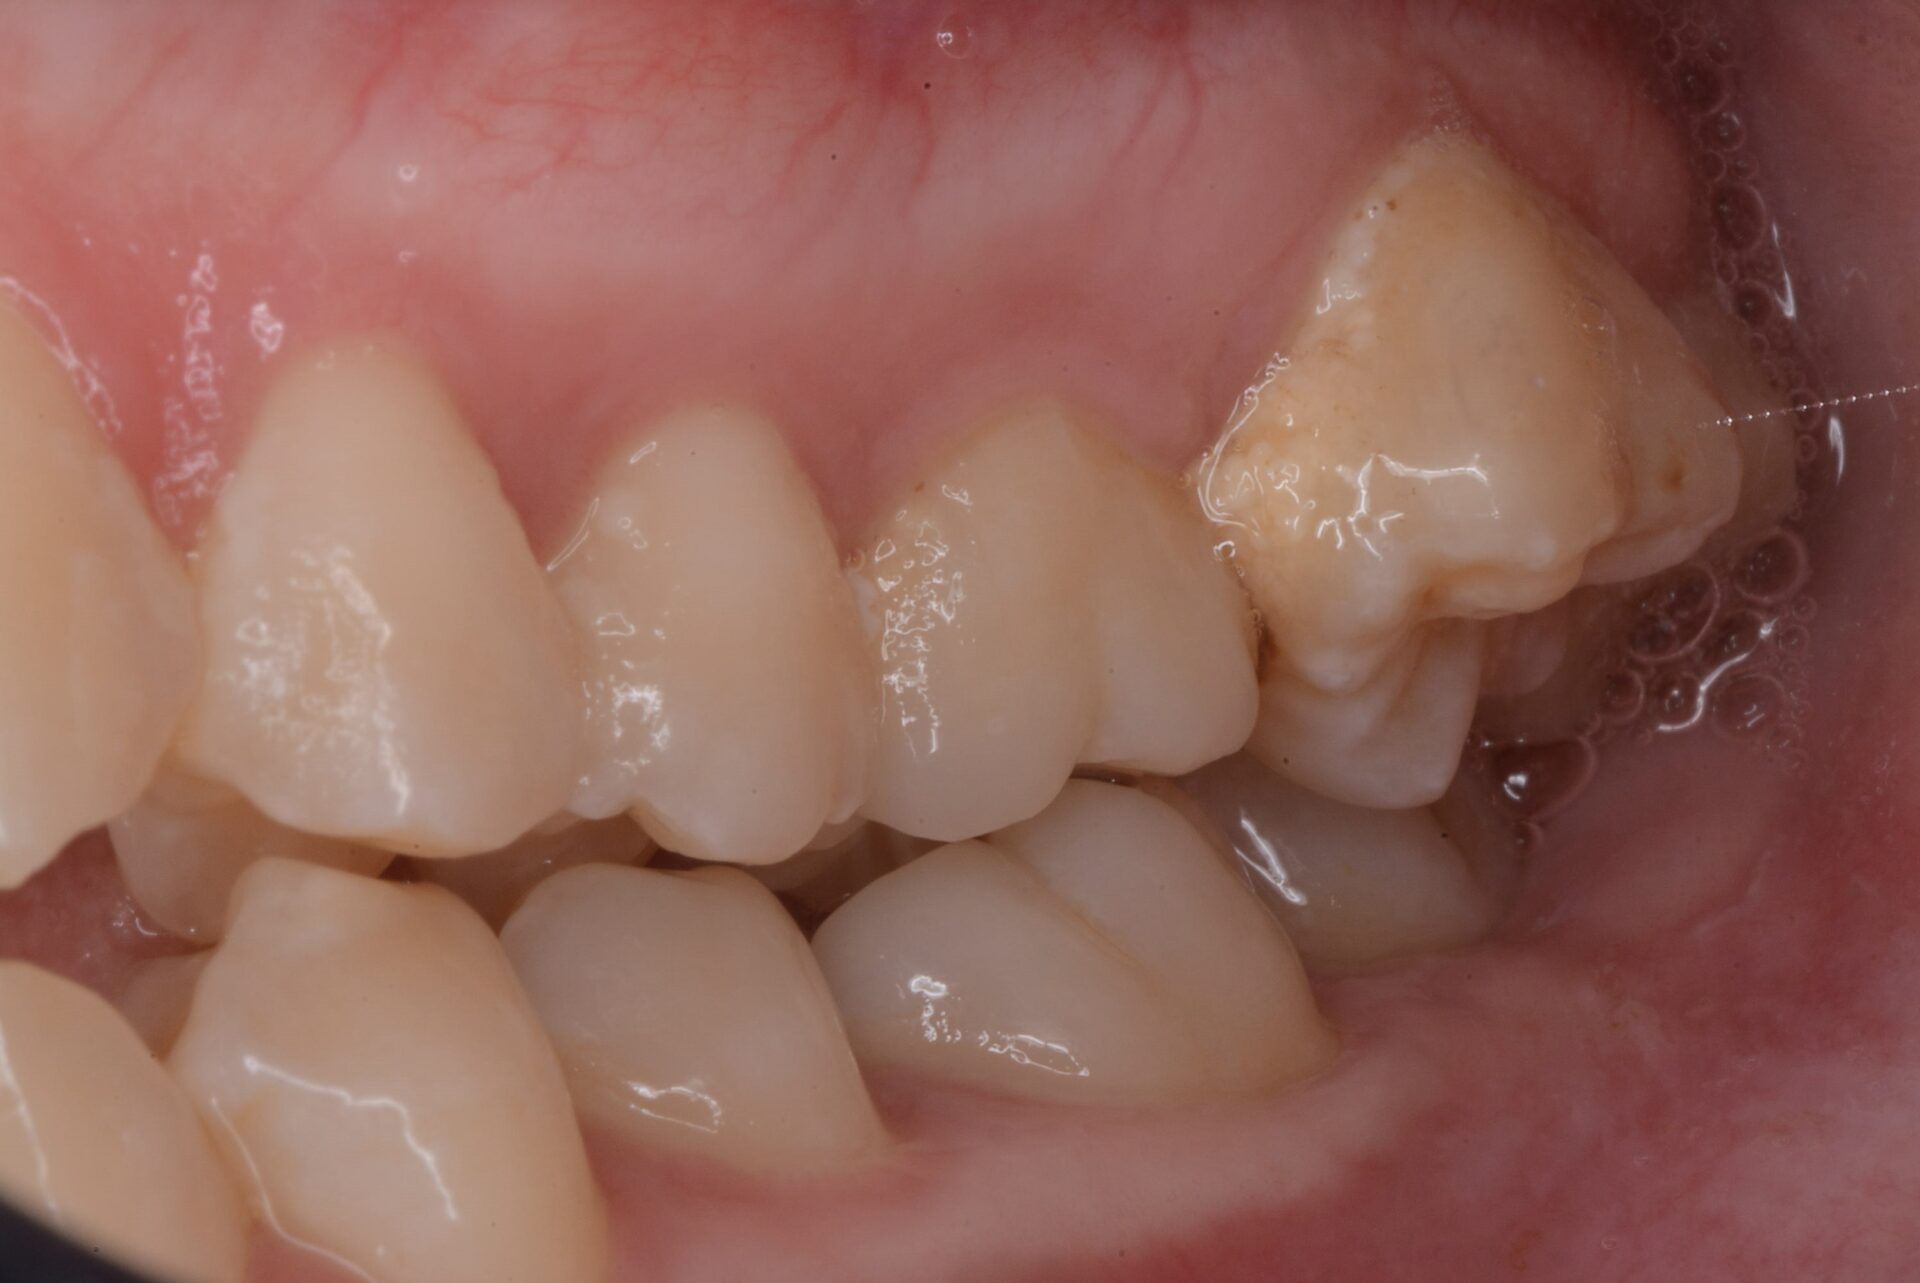

左側上顎第2大臼歯が随分と外側に生えている。そのため下顎とすれ違ってしまっていた。

口蓋に痛みはないが大きな腫れがある。その腫れのため大臼歯は外側に生えてきてその後も少しずつ動かされてしまったと思われる。矯正治療を進めても臼歯部はほとんど内側に動いてこない。生検により多形腺腫と診断される。